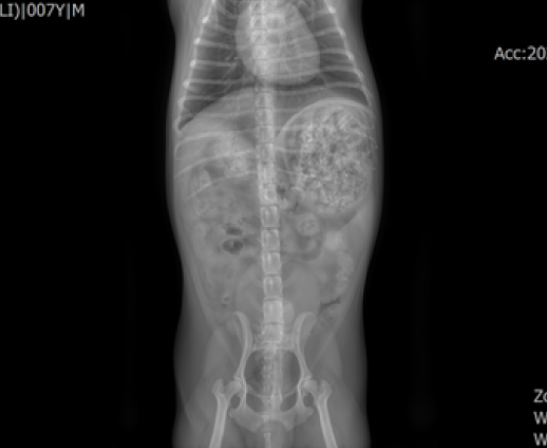

쓰레기통을 뒤져 닭 뼈를 섭취한 7살 치와와 환자가 내원하였으며 X-ray 검사 결과 위장관 내에 날카로운 닭 뼈 부스러기들과 음식물이 정체되어 있는 것을 확인하였습니다.

내원 당시 별다른 임상 증상은 없었으나 x-ray 상에서 위장관 내 닭 뼈 부스러기와 음식물이 다량 보였습니다.

그리고 유문부 쪽에서도 상대적으로 큰 닭 뼈가 관찰되었습니다.

먹은 후 시간이 조금 지난 상태였지만 위장관 내에 계속 저류하고 있는 상황이었습니다.